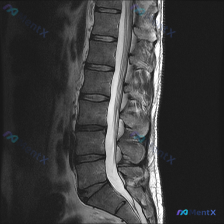

整理到一份腰椎MRI的影像分析资料,最初的问题很直接:「这张图里能观察到脊柱侧弯吗?」 先看已有的影像信息: - 序列:腰椎MRI T2矢状位 - 明确发现:L1/2到L5/S1椎间盘弥漫性脱水低信号,L4/L5、L5/S1向后膨出压迫硬膜囊前缘,部分椎体终板有许莫氏结节,生理前凸存在,序列尚可,无...

整理到一份腰椎影像资料,有点意思,拿出来和大家讨论。 资料是腰椎矢状位T2加权像,先说说能看到的表现: 1. 多节段椎间盘信号明显减低(黑盘征),L3/4、L4/5、L5/S1椎间隙还有不同程度塌陷; 2. L3/4、L4/5、L5/S1都有椎间盘突出,硬膜囊受压,L4/5、L5/S1看起来受压更明...